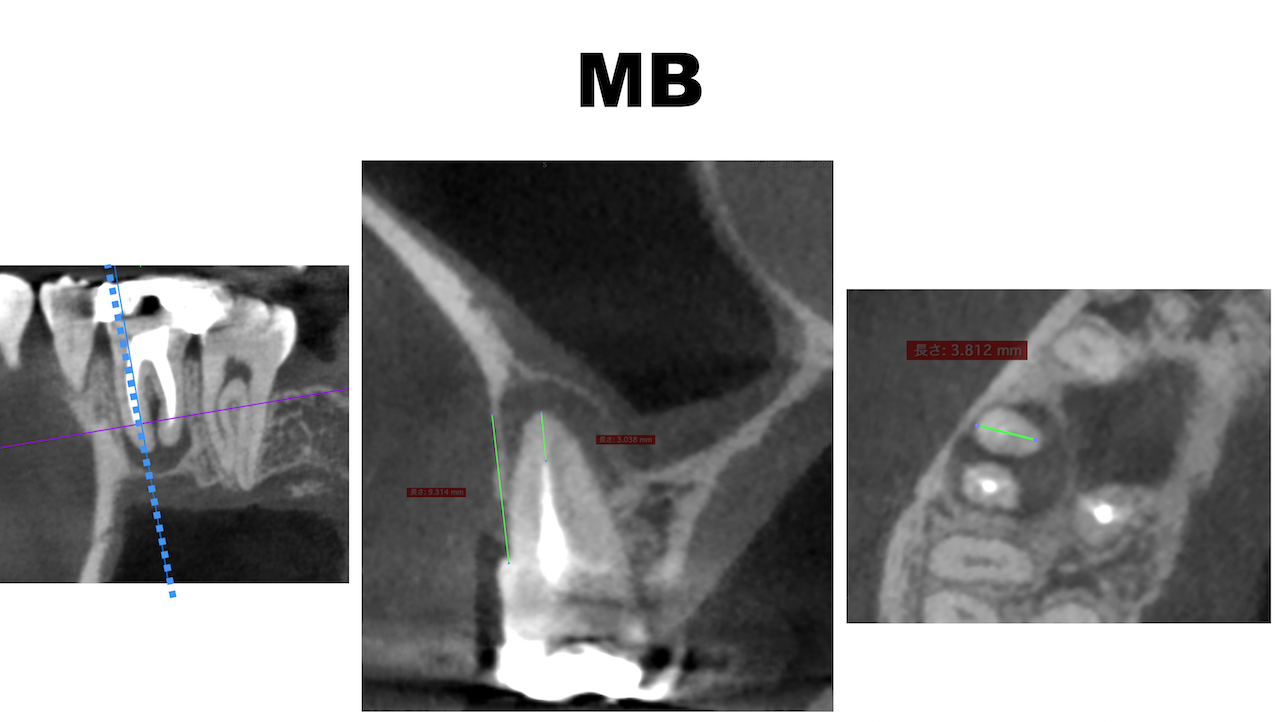

#3 MB

MBとDBは近接し、3mmで切断した際の頬舌的な厚みも3.5~4mmだ。

そしてMB1, MB2は近接している。

またMBもDBも近接している。

以上のことからこのApicoectomyは容易であると私にはわかる。

このような絵を作り、ユニット横に貼り付ける必要があるだろう。

私はこの作業も数分で終了している。